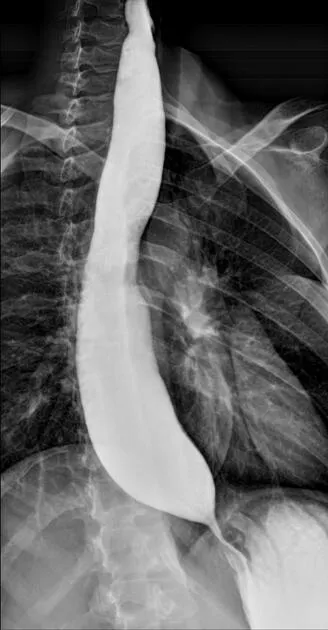

- Barium swallow shows "bird-beak" sign.

- Achalasia involves loss of the myenteric plexus, causing failed LES relaxation and a "bird-beak" sign.